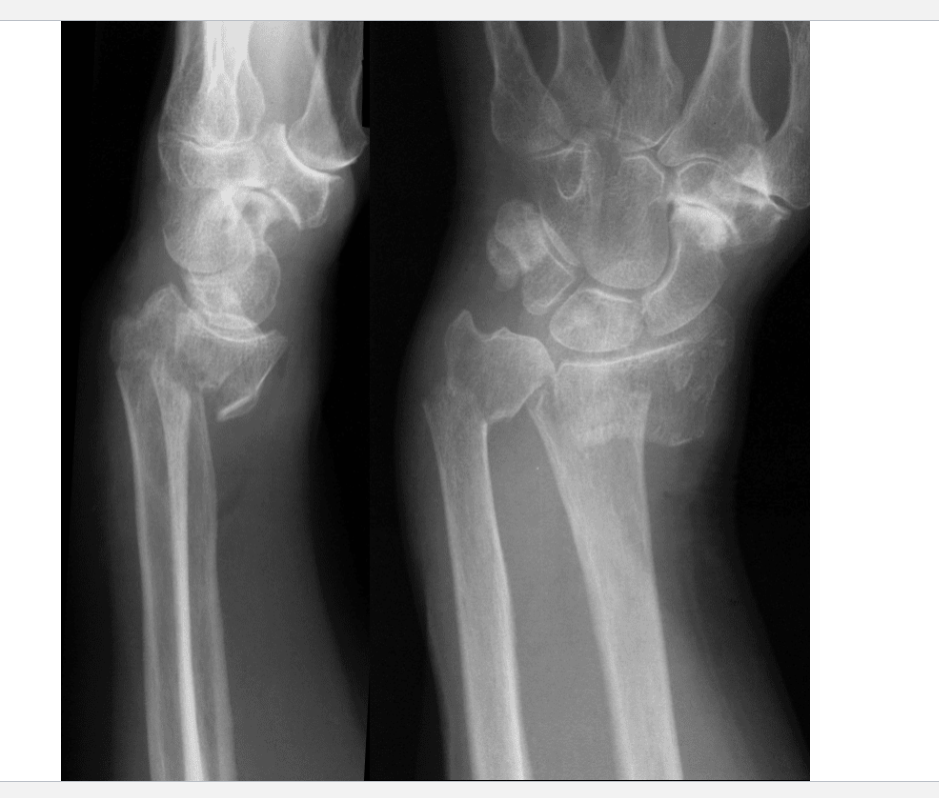

What is this?

Smith fracture